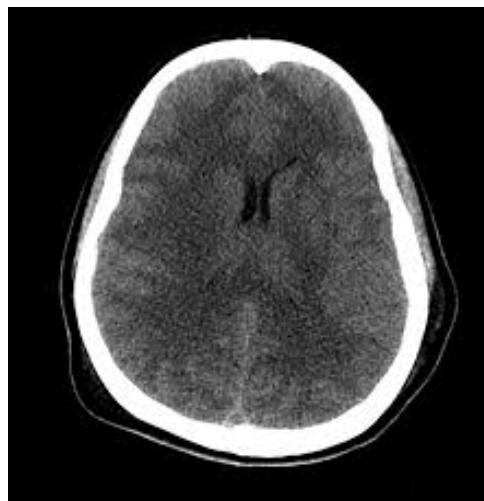

- Cerebral Edema: (Risk in young/new-onset). If neurologic change occurs Mannitol before CT.